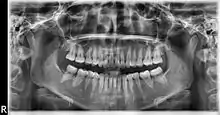

Ortopantomografía

La ortopantomografía o radiografía panorámica es una técnica radiológica que representa, en una única película, una imagen general de los maxilares, la mandíbula y los dientes. Por tanto, es de primordial utilidad en el área dentomaxilomandibular.

Su papel en el diagnóstico odontológico, no solo de los dientes sino también del maxilar y mandíbula, es fundamental. Sin la ortopantomografía, el odontólogo perdería una gran ayuda en la mayoría de las especialidades de su campo. Prácticamente, es utilizada de forma sistemática en odontología, llegando a ser un arma diagnóstica rutinaria. El valor diagnóstico de la ortopantomografía en cirugía bucal, implantología, ortodoncia, periodoncia y en patología oral y dental está claramente demostrado.

El término de radiografía panorámica es el más comúnmente utilizado, ya que la radiografía resultante muestra una visión panorámica de la cara y parte inferior de la cabeza. Laudenback describe la ortopantomografía como uno de los inventos radiológicos más originales de los últimos decenios. El 40 % de los hallazgos patológicos principales y secundarios se descubren a partir de ella. Amplía el campo de diagnóstico en un 70 % y reduce la dosis de radiación de la superficie cutánea en un 90 % con respecto a las series radiográficas periapicales.